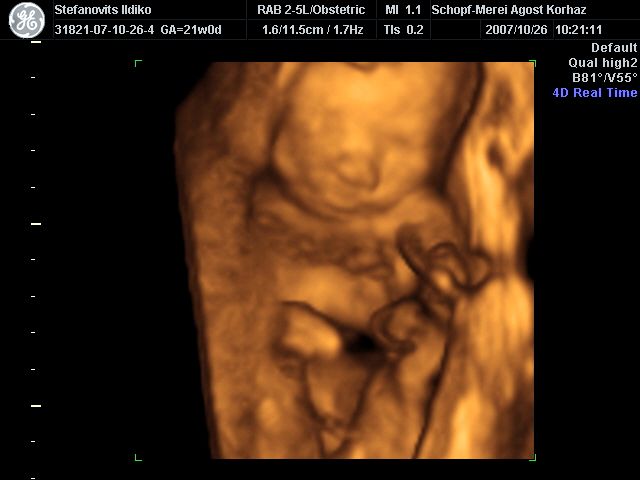

4D Ultrahang - 21+1 (07/10/26, Bp.)

4D - 2